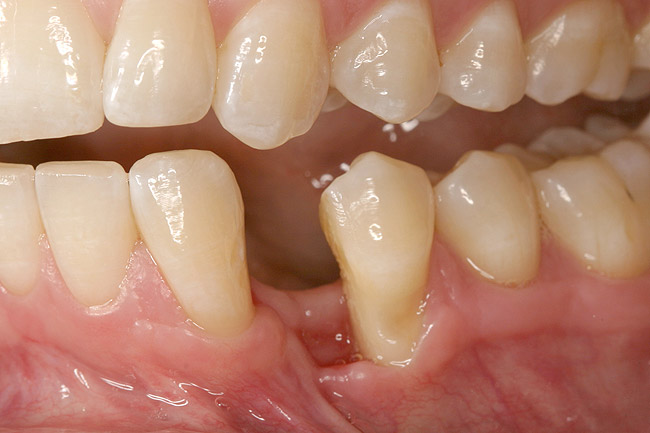

A 28-year-old Caucasian female presented to the periodontist with a complaint of a mobile implant in the site of tooth No. 22 (Figure 2 and Figure 3). The patient had a congenitally missing tooth No. 23. No. 22 had erupted into site No. 23, leaving a vacancy at site No. 22, and was the reason for the original implant at site No. 22.

The patient had no medical concerns and had a history of an implant placement in December 2002 when she was 25 years old. In February 2005, she presented with a mobile implant and an associated advanced peri-implantitis. Radiographic review at the initial examination demonstrated significant destruction of the dentoalveolar ridge around the implant as well as around the adjacent natural dentition. Emergency-based treatment involved surgical implant removal only and debridement of the infection (Figure 4 and Figure 5). Following uneventful healing, an advanced ridge defect was apparent at the edentulous site and moderate and advanced attachment loss noted at No. 22D and No. 21M, respectively (Figure 6 and Figure 7). This case demonstrates bone loss of two separate origins: lack of bone because of tooth agenesis and destruction of bone from inflammatory peri-implantitis.

Figure 12  Right buccal view showing posterior occlusion established, canine guidance and proper space appropriation around peg lateral tooth No. 7, and intruded worn incisors.

Figure 12